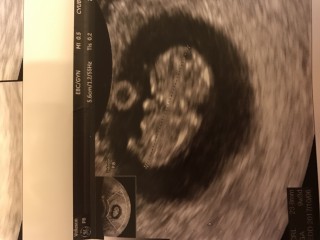

CRL2.77cmでした。だいたい平均くらいかと思います。 5w5dのときには人の形には見えなかったのですが、今回の診察で2頭身になり、手足も見えるようになりました。とても可愛らしく思います。 関係ありませんが、担当の先生がいつもと違う方で、結構ぐりぐりやられたので地味に痛かったです…。